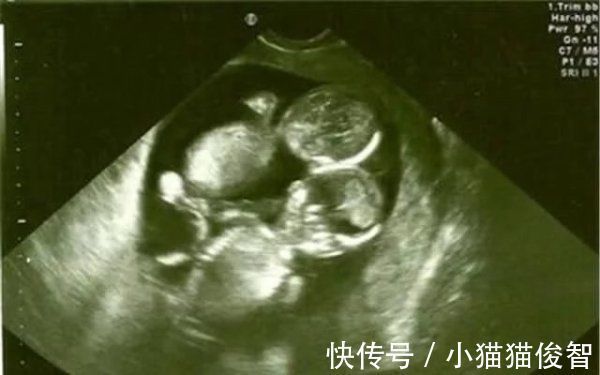

知道去年年底,陈女士的月经一直不来,用验孕棒一查才发现怀孕了,她和老公喜极而泣。对于这个来之不易的胎儿,家人给出了足够的重视,婆婆从乡下赶过来照顾她。怀孕三个月的时候查出是双胞胎,这让全家人都兴奋不一样,都说车女士厉害,不怀孕则罢,一怀孕就是双胞胎,给家里挣足了面子,婆婆逢人就夸儿媳。

然而怀孕第五个月排畸检查却让全家人掉入了谷底,医生告知这是一个连体婴儿,脑袋连在一起了,建议立马做引产手术。不然生下来不但拖累家庭,对孩子也是一种不负责。车女士和老公瞬间感觉到整个天都塌了,此时孩子已经有胎心了,陈女士能明显感觉到宝宝强有力的跳动。

医生说做四维彩超的时候,刚好两个胎儿的头紧紧靠在一起,所以被误认为是连体婴,没想到却是兄妹情深,相互相依。产房外的家属得知后也是相拥而泣,爸爸更是对两个更出生的婴儿说,以后一定要好好孝顺你妈,是她的坚持才有你们俩。